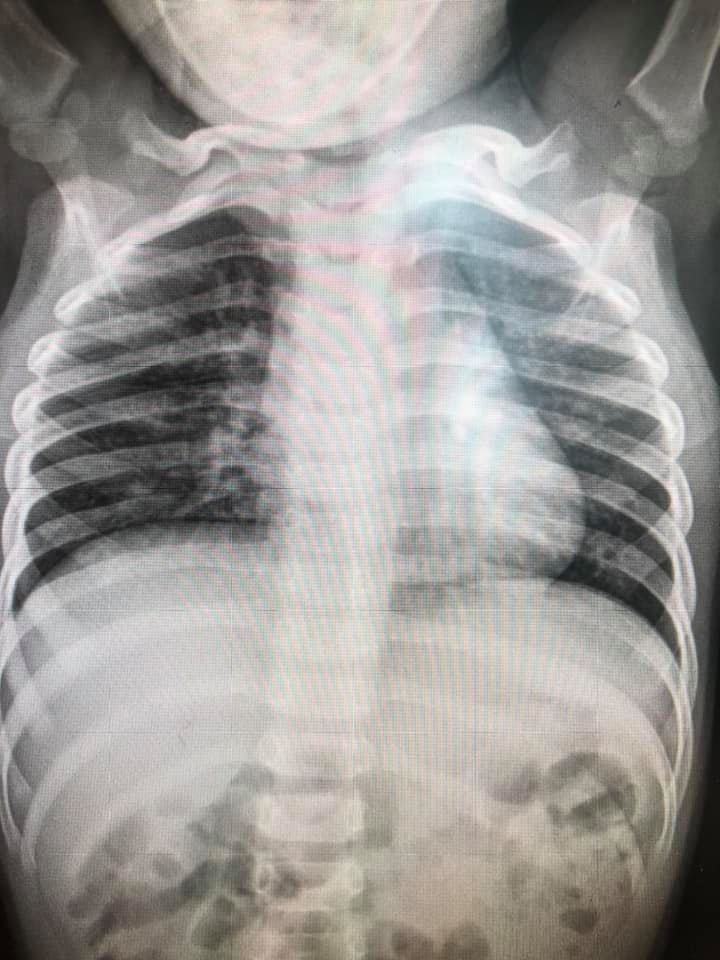

ล่าสุด วันที่ 6 พฤศจิกายน 2563 เฟซบุ๊ก Infectious ง่ายนิดเดียว ได้โพสต์ภาพฟิล์มเอกซเรย์ปอดเด็กที่ติดเชื้อไวรัส RSV 10 คน ที่เข้ารับการรักษาที่โรงพยาบาล โดยได้รับการวินิจฉัยว่ามีอาการหลอดลมอักเสบ ปอดอักเสบ โดยฝ้าสีขาวคือตำแหน่งทีติดเชื้อ สีดำคือปอดปกติ พร้อมระบุข้อเท็จจริงของ RSV ดังนี้